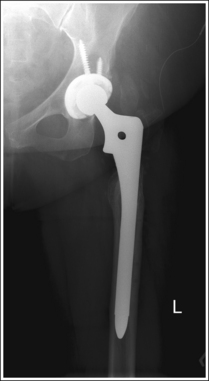

The femoral head or neck is at the center of the exposure field. The acetabulum, greater and lesser trochanters, femoral head and neck, and half of the sacrum, coccyx, and symphysis pubis are included within the collimated field. Any orthopedic apparatus located at the hip are included in their entirety.

• A 10- × 12-inch (24- × 30-cm) IR placed lengthwise should be adequate to include all the required anatomic structures. A larger IR and lower centering point may be necessary to include hip orthopedic apparatus (Figure 7-7).

The femoral neck is at the center of the exposure field. The acetabulum, femoral head and neck, greater and lesser trochanters, and ischial tuberosity are included within the collimated field. Any orthopedic apparatus should be included in its entirety.

• A 10- × 12-inch (24- × 30-cm) IR placed lengthwise should be adequate to include all the required anatomic structures. A larger IR and lower centering point may be necessary to include hip orthopedic apparatus (Figure 7-19).